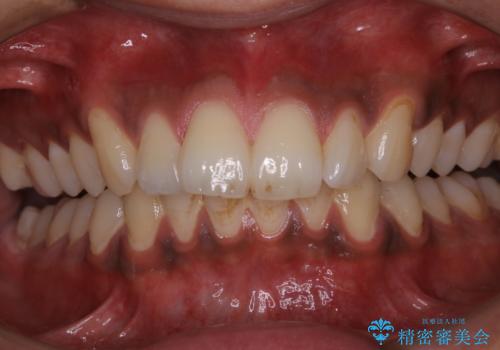

歯についたタバコのヤニをPMTCで綺麗に

- 電子タバコを吸う習慣があり、ステインがついてしまっている見た目が気になるとのことで来院されました。ステインだけではなく、歯石も全体的に付着していたためPMTC60分コースを行いました。

PMTCは、歯に付着した汚れを除去していくため、着色が気になる場合にも行うことができます。ご自身でのセルフケアだけで着色を落とそうとすると、逆に歯を傷つけてしまったり、精密に汚れを除去できないこともあります。また、日常生活で着色しやすい飲食物を避けたりすることはストレスに感じてしまったり、あまり現実的ではありません。